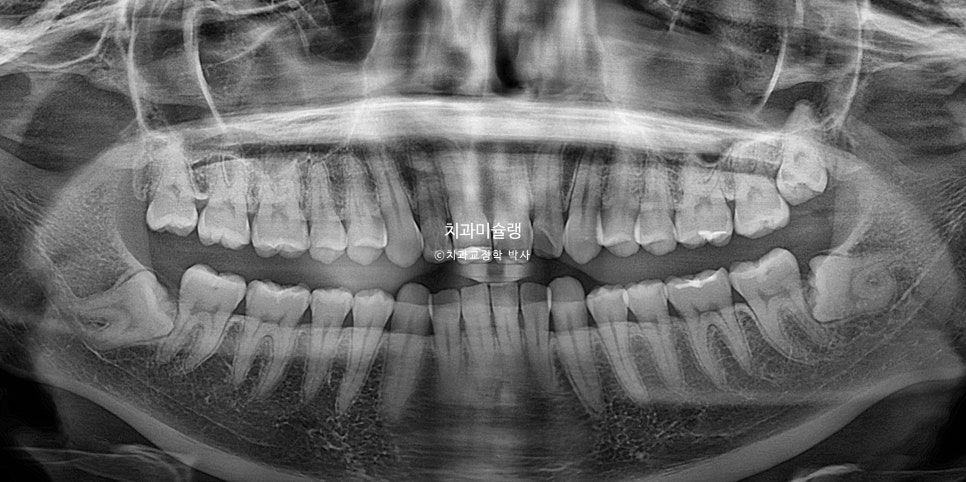

환자 초진 상태

2023년 4월 초진

23년 4월, 교정치료를 위해 오신 20대후반 환자입니다. 실제론 앞니가 전반적으로 작은편임에도 불구하고 사진에서 앞니가 유독 커보이는건 돌출되어있기 때문입니다.

앞니 2개가 유난히 돌출되어 있습니다.

앞니뿐 아니라 어금니 교합관계가 2급입니다.

악궁이 좁고 뾰족합니다.

한쪽 사랑니가 깨끗하게 잘 나와있습니다. 반대쪽 사랑니도 곧 내려오겠죠.